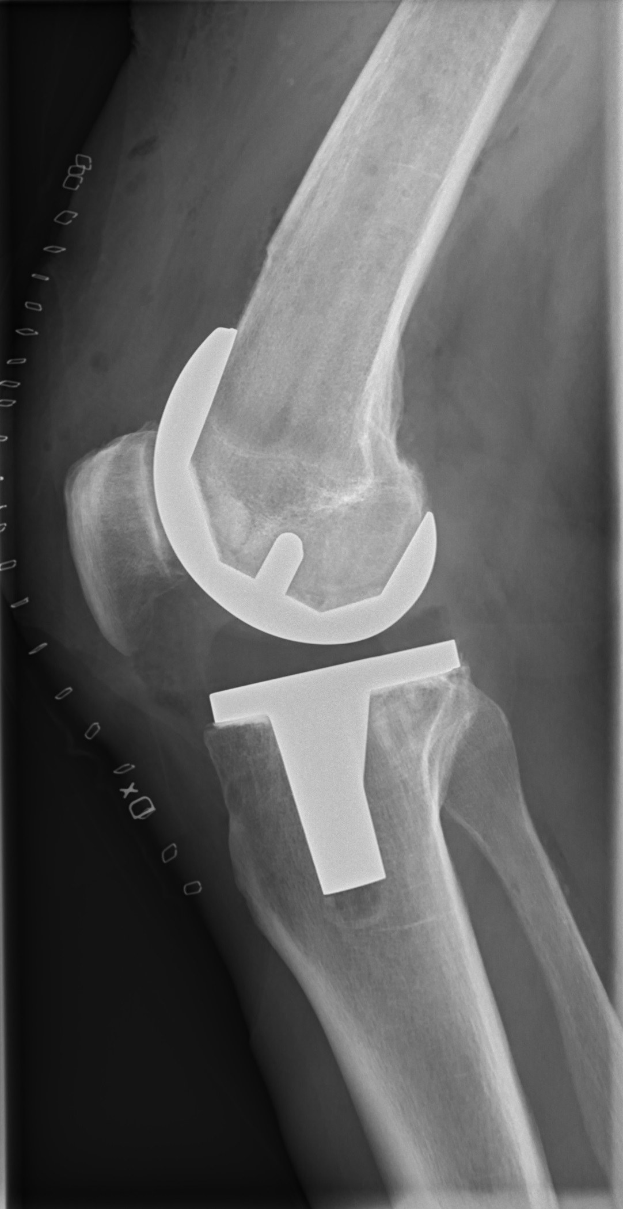

Brackelmanns Ausfall begann nach anhaltenden Problemen im linken Oberschenkel. Ärzte stellten später eine Verkalkung fest, die in München operativ entfernt werden musste. Es ist nicht das erste Mal, dass Verletzungen seine Saison unterbrechen – bereits zuvor hatten unplanmäßige Pausen seine Einsatzzeiten beeinträchtigt.